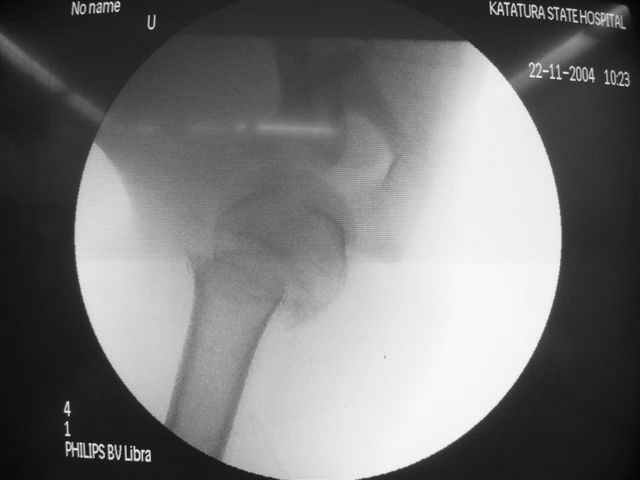

Женя, а как ты водишь спицы, в смысле, как делаешь входное отверстие, и как в него проводишь V-спицу? А то о дна из спиц, та, у которой не дошла до головки одна палочка буквы V, как-то выглядит на рентгенограмме, как будто или через очень большое отверстие введена, или каждая половинка через отдельные отверстия.

В чем ты видишь причину вторичного смещения?

Мне кажется, проблема в том, что не все концы спиц зашли в головку, и зашедшие - недостаточно далеко прошли.

Спицы провожу по передней и задней поверхностям плечевой кости через 4,5 мм отверстия на разных уровнях.

Идеей презентации случая была демонстрация важности постоп Рг - хотя казалось бы все было сделано под флюороскопическим контролем и интраоперационно подозрений на нестабильность не возникло, а такая вот

неожиданность...

Уточни - обе части буквы V вводишь в одно отверстие? А то по снимкам выглядит, что в разные.

V-спица проводится через 4,5 мм отверстие. Видимо, из-за разной длины вторая половина спицы *пролетела* мимо отверстия, что и привело к вторичному смещению костных фрагментов.